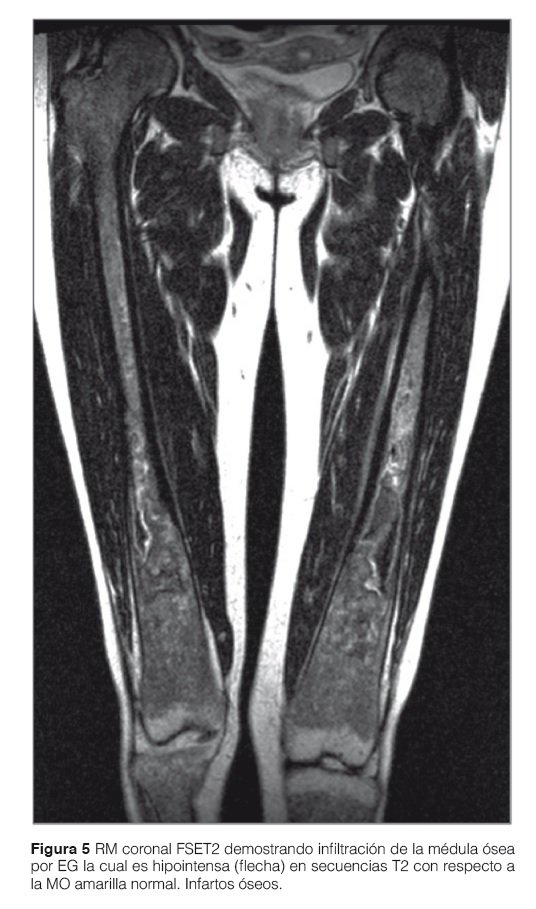

La combinación de secuencias SE T1 y Stir permite una exacta valoración de la médula ósea. El reemplazo de la médula ósea habitual por células de Gaucher (hipointenso) se ve reflejado claramente en las secuencias T1 y T2 sin saturación de grasa gracias a su calidad anatómica y alto contraste con la grasa hiperintensa normal de la MO grasa o amarilla. En secuencias SE T1 comprobamos el grado de infiltración, tipo de infiltración (homogéneo o heterogéneo) y el daño estructural óseo. En secuencias STIR se evalúa también la infiltración de la MO y pero principalmente y gracias a su gran sensibilidad al edema óseo (hiperintenso en Stir) se evalúa la presencia de lesiones agudas, destacándose las crisis óseas, los infartos, la necrosis avascular y las fracturas (Fig. 5).